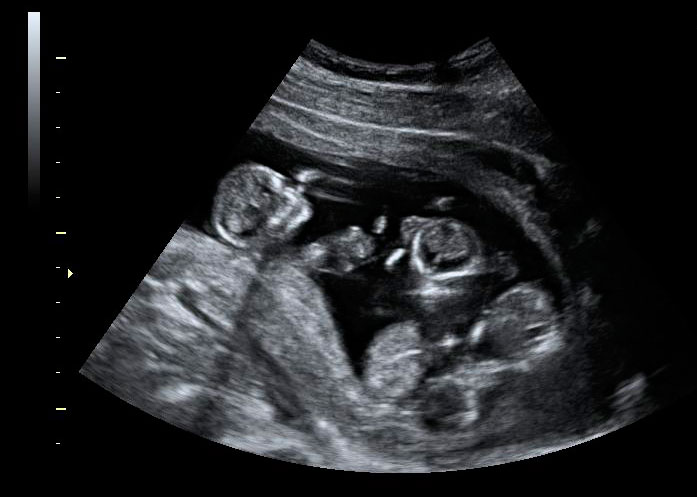

Ecografía 4D de semana 13: Bebé moviéndose

Es impactante ver los movimientos de este bebé de 13 semanas de gestación, que parece bailar en un escenario. En la ecografía 4D se aprecian perfectamente todas sus estructuras básicas (cabeza, tronco, extremidades...), incluso los genitales masculinos. Destaca la bipedestación de la figura -se encuentra erguida-, que parece más humana de lo que podríamos imaginar a esa edad gestacional.

Ecografía en 4D. Bebé de 13 semanas de gestación moviéndose

Tras ver esta ecografía, cuesta creer que este bebé tenga tan sólo 13 semanas de gestación. El bebé tiene unos movimientos muy humanizados a pesar de su corta edad gestacional.